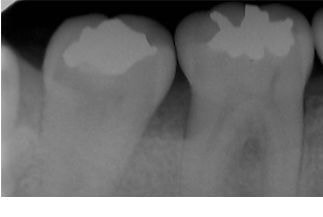

問診・視診・打診・温度診・レントゲンなどの検査を行っても原因が特定できない場合でも、マイクロスコープで検査を行うことで何が原因になっているか特定できる症例はたくさんあります。

根管治療後の痛みの原因は、実は治療している歯でない場合や不適切な根管治療によって起こる場合、急性の歯髄炎によるものや急性根尖性歯周炎によるものなど様々です。